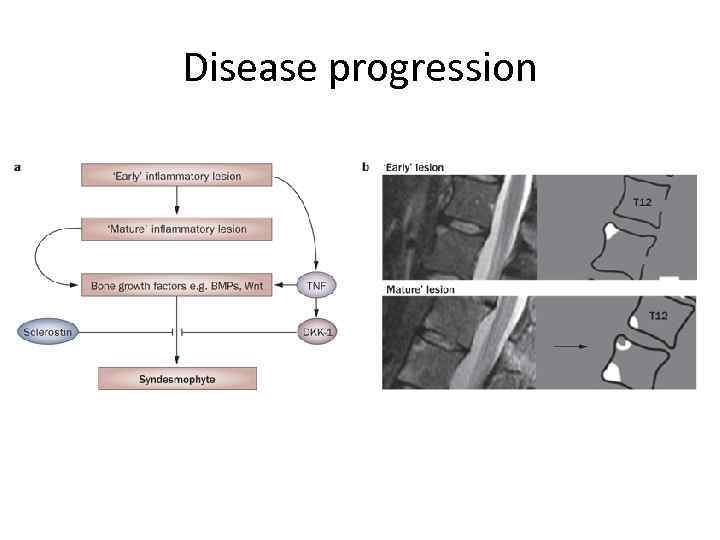

Disease progression